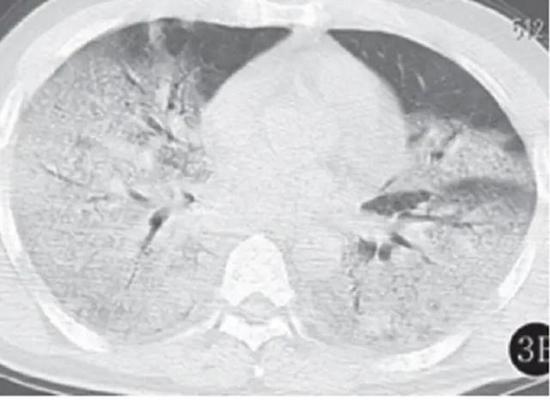

若病毒大量復制,或者患者免疫功能較弱時,會發展為危重癥。此時病毒會攻擊多個肺葉,肺泡損傷彌漫,病變范圍擴大、融合,造成雙肺實變,即從CT上看,患者的肺部呈一大片的白色狀,醫學上稱之為“白肺”。這種情況會嚴重影響肺換氣,患者需要持續吸氧。

▲白肺(圖片來自網絡)

按照國家衛健委發布的新型冠狀病毒肺炎試行第六版診療方案之中的臨床分型,新冠肺炎分為輕型、普通型、重型及危重型。在患者的肺部CT中,輕型者沒有比較明顯的肺炎改變;普通型者以肺部出現局限性斑片狀或很多節段性片狀“病灶”為主(圖②);重型者雙肺可出現較多的白色小斑片“病灶”,部分融合成大片狀“病灶”(圖③);危重型者會有“白肺”表現(圖④)。

▲從上到下依次為普通型、重型及危重型新冠肺炎患者的肺部CT表現(圖片來自網絡)